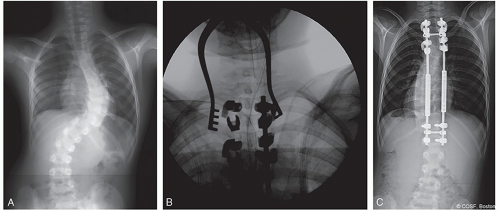

Occasionally shorter constructs (Figure 8.2) can be employed, but T2-L3 is typically a safe and predictable construct for most neurotypical patients